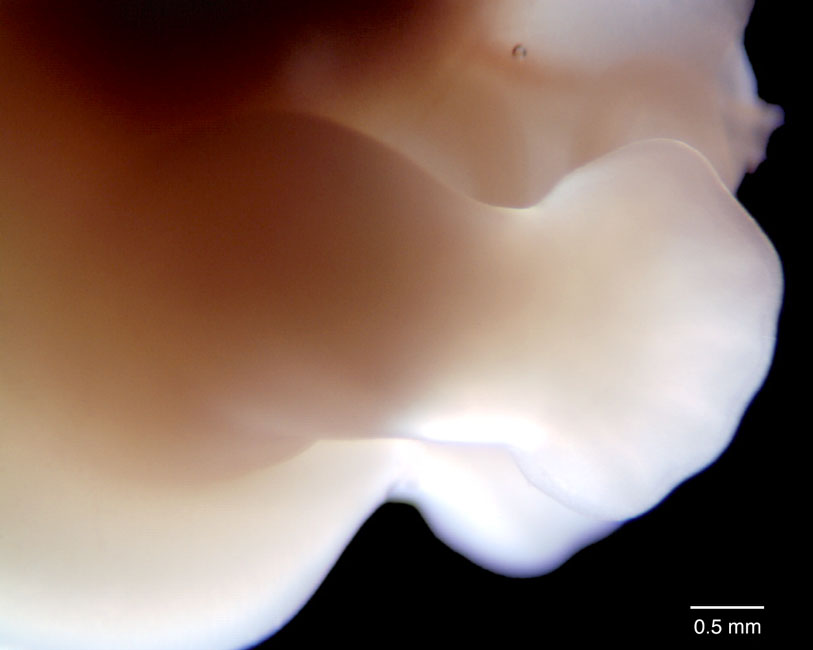

Day 50 Human Embryo

human embryo photograph